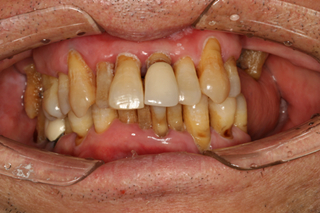

郭老口内照片